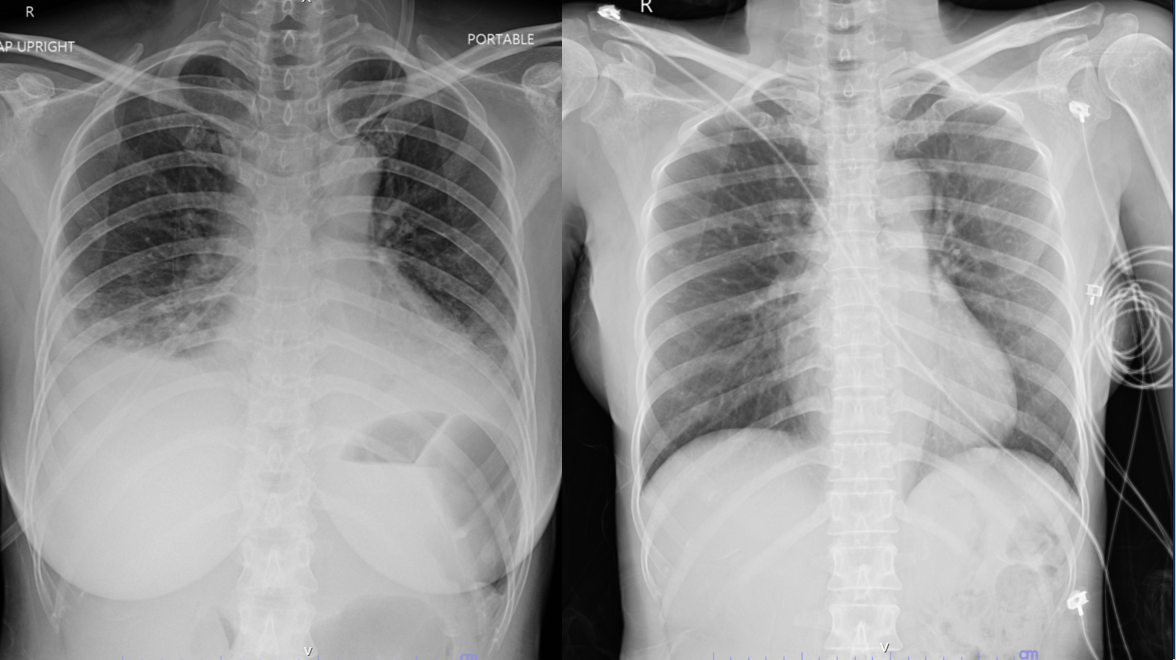

Initial ECG showed sinus tachycardia with low voltage QRS and minimal ST elevation in inferior leads. Chest X-ray revealed cardiomegaly, bilateral infiltrates, and pleural effusions consistent with acute heart failure.Laboratory findings: troponin I 1,400 ng/L, NT-proBNP 19,903 pg/mL, lactate 5.7 mmol/L, AST 483 U/L, ALT 611 U/L, hsCRP 6.31 mg/dL, Echocardiography showed LVEF 29.4% with global hypokinesia, impaired RV function (TAPSE 12 mm), and mild pericardial effusion (0.4 cm).